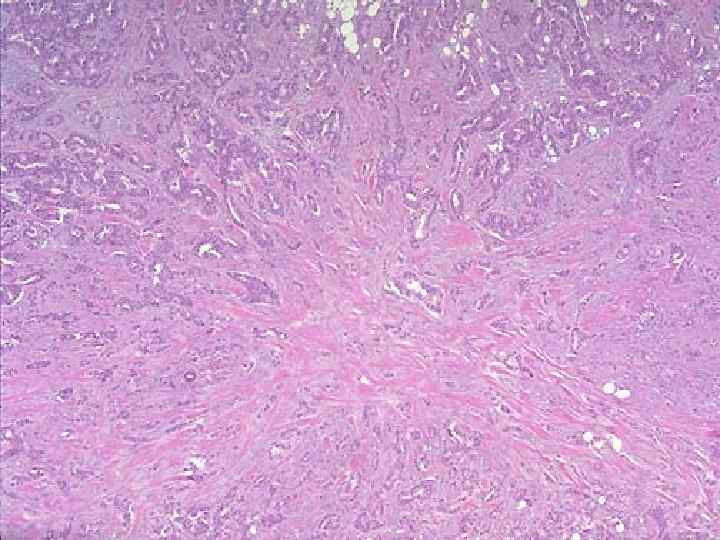

ДГПЖ